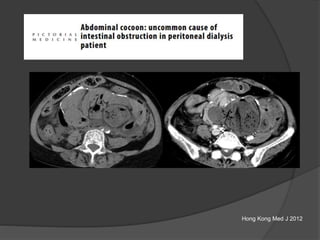

Case 2 Diagnosis: “Cocoon

peritonitis”

•AKA sclerosing

encapsulating peritonitis

•Rare cause of bowel

obstruction due to fibrotic

encapsulation of the bowel

forming a sac or cocoon

•May be idiopathic or

secondary to chronic

peritoneal dialysis, TB,

sarcoidosis, GI malignancy,

fibrogenic foreign material

•Treatment –Surgical

removal of the covering

membrane

Hong Kong Med J 2012

Case 13: 45 M with abdominal pain

Case courtesy: Francesco Danza, MD

Peritoneal carcinomatosis Thick enhancing membrane

around a conglomerate of

small bowel loops in the

center “cocoon”

Diagnosed with adenocarcinoma lung 6 months ago

Case 13 Diagnosis:Cocoon peritonitis

sarcoidosis, GI

malignancy, fibrogenic

foreign material